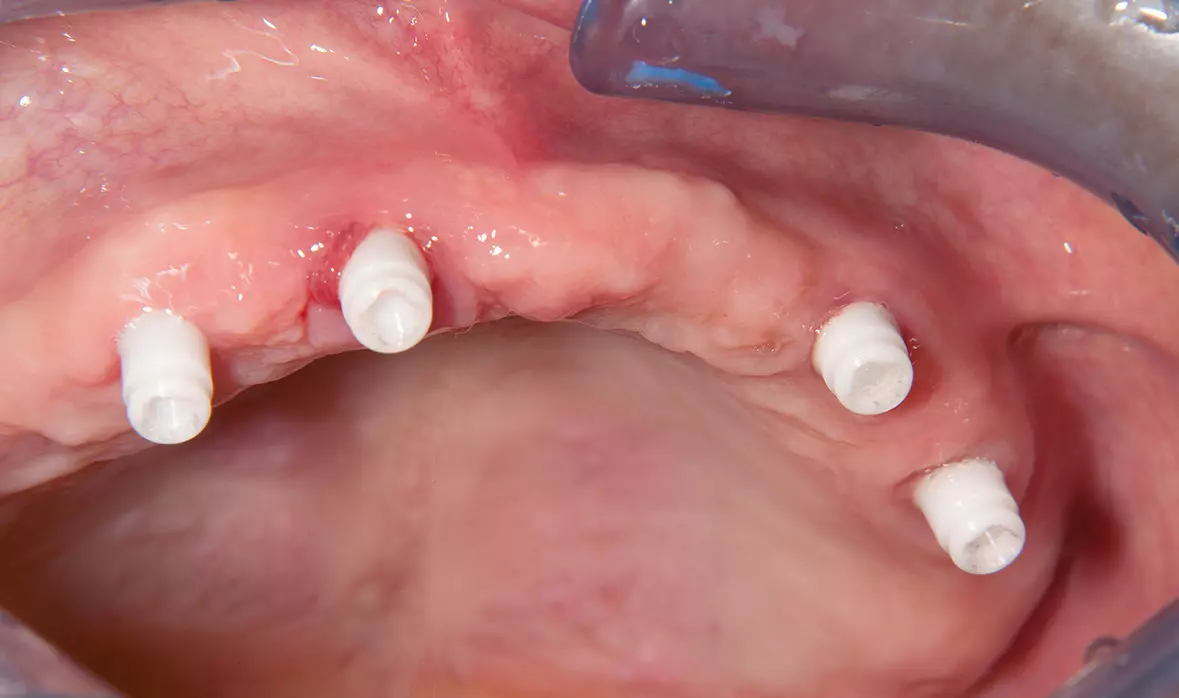

Abb. 19: Nach drei Monaten Einheilzeit, Entnahme der Healing Caps und Aufsetzen der Abdruckpfosten. Dr. Michael Leistner

Abb. 19: Nach drei Monaten Einheilzeit, Entnahme der Healing Caps und Aufsetzen der Abdruckpfosten.